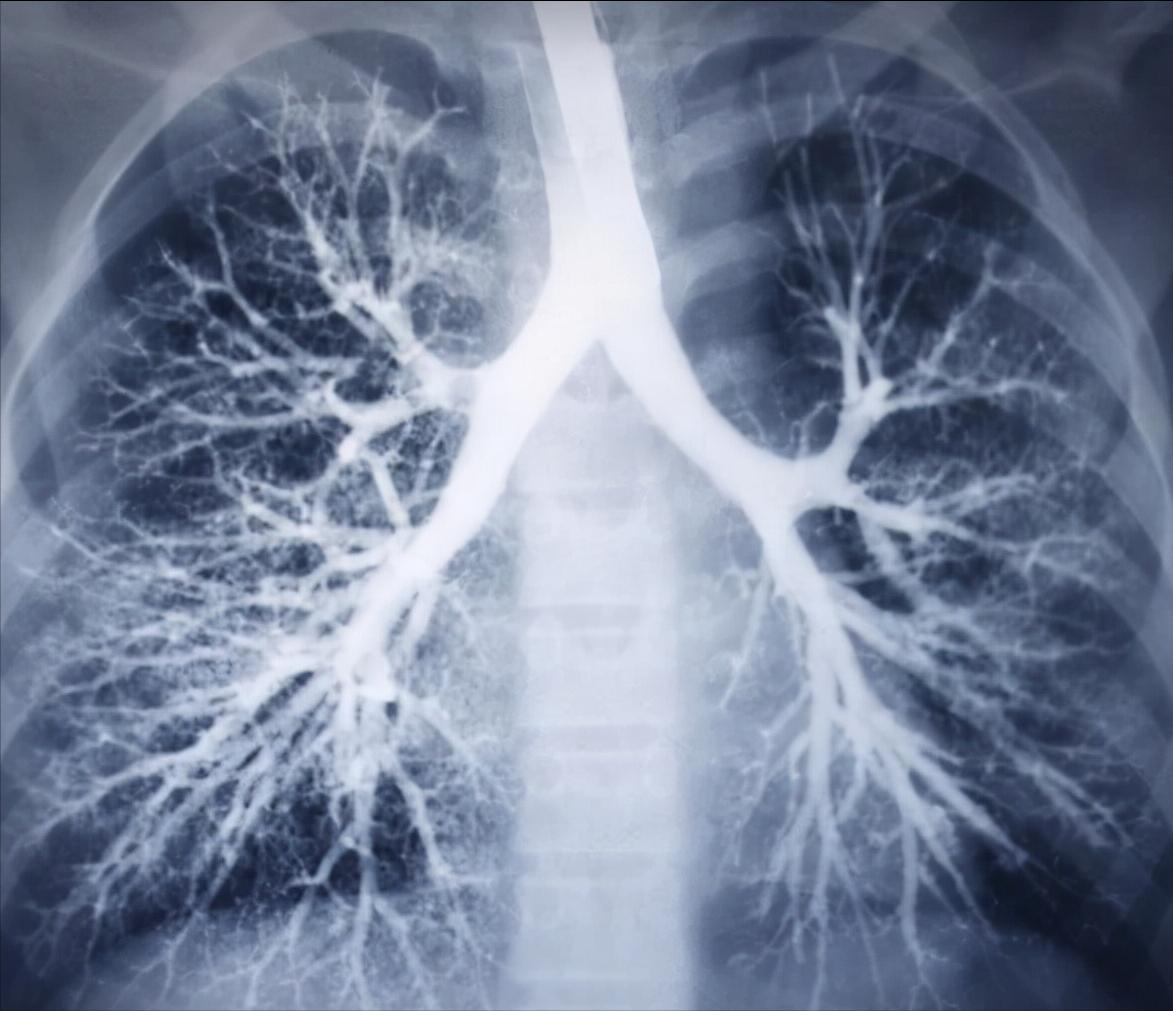

白色的树杈就是您的血管、气管、淋巴影子呦

肺纹理,其实就相当于一棵树的树枝,在影像学上因难以穿透,所以在片子上一般呈现的是白色条纹状,跟树杈一样;那有些人也好奇树叶呢,相当于啥呢?树叶就是肺泡;

在肺里,哪些东西相当于树枝呢,其实就是肺里面的血管、气管、甚至淋巴管,很明显这些都是管状的,呈条索样;